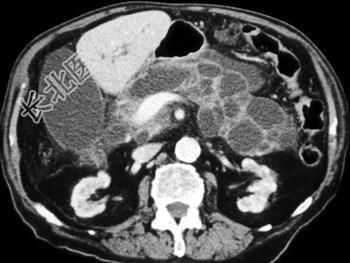

- 单项选择题根据所提供的图像,可除外下列哪种诊断 ( )

A、胰腺导管内乳头状黏液性肿瘤

B、胰腺囊腺瘤

C、胰腺假性囊肿

D、胰腺癌

E、以上都不是